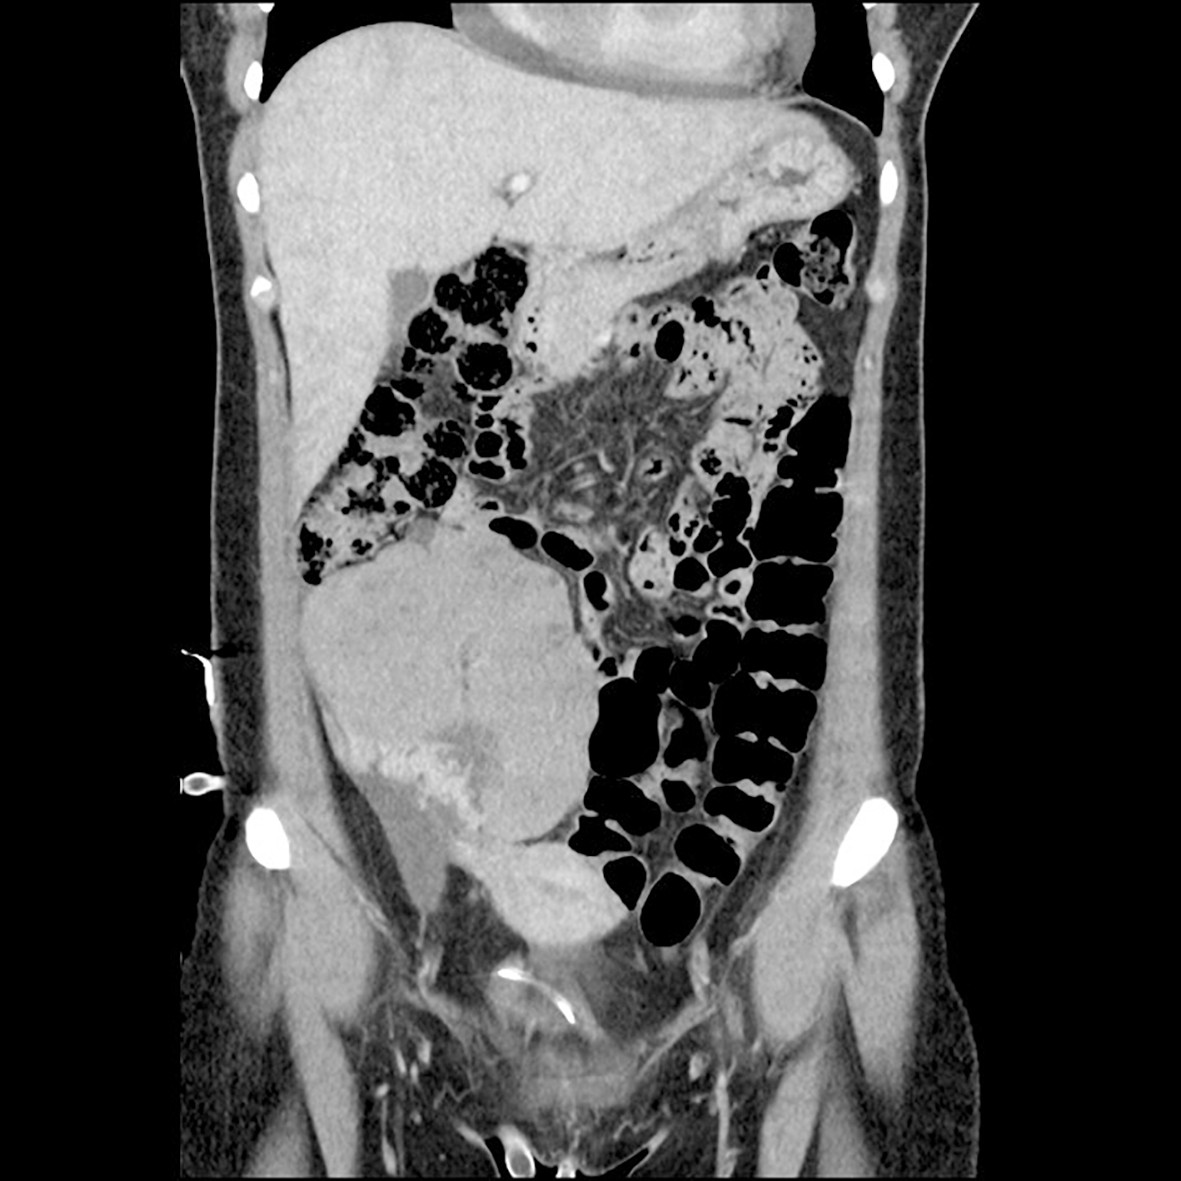

Det vart vidare utført ytterlegare bildediagnostikk, med CT thorax, abdomen og bekken. Denne verifiserte funna frå ekkokardiografien, ein ekspansiv prosess i høgre hjartehalvdel med perikardvæske. I tillegg vart det funne ein stor ekspansiv prosess til høgre i abdomen som målte 11 x 8 cm, med varierande tettleik og kontrastopplading, forkalkingar og rikeleg vaskularisering. Det vart også påvist mindre kontrastladande oppfyllingar og fri væske i fossa Douglasi (fig 2).